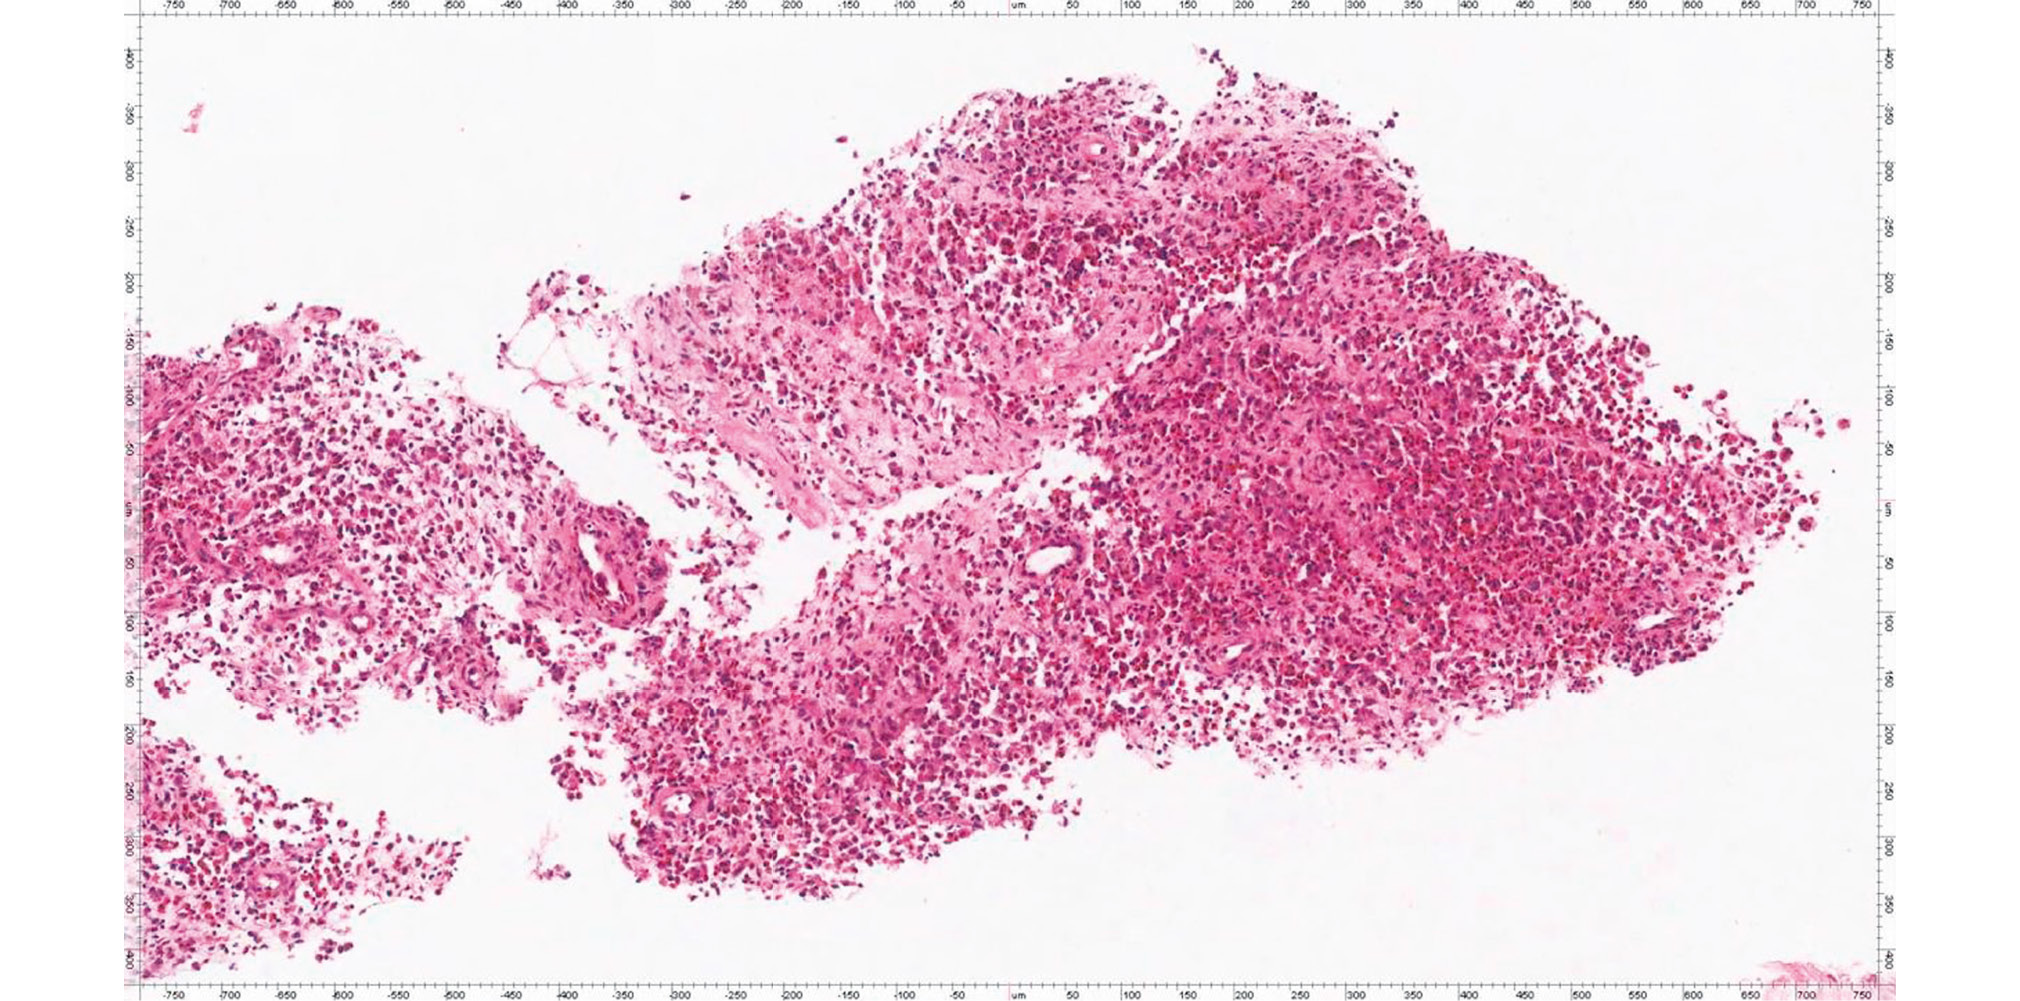

CT-guided 18G needle biopsy was performed from the wing formation of the left iliac bone (Fig. 3). The histological study (No. 2017-10802-01) concluded on the morphoimmunohistochemical presentation, which is most consistent with Langerhans cell histiocytosis (eosinophilic granuloma, histiocytosis X) (Fig. 4).

Fig. 3. The process of needle biopsy by computed tomography.

Fig. 4. Histological specimen: fibrovascular tissue fragments with polymorphic-cellular infiltration consisting numerous granulocytes, including an abundance of eosinophils, plasma cells, and individual cells with bean-shaped nuclei are noted. Hematoxylin-eosin staining ×200.